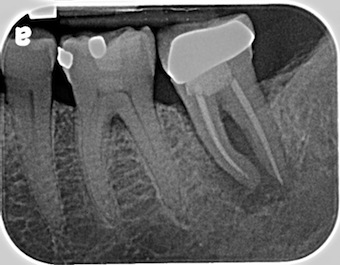

Implant-Supported Restoration for a Lower Second Molar

How much treatment is required to prepare this site for a dental implant-supported restoration? Dental implants have improved the options available to our patients for solutions related to missing teeth. There are many advantages to preserving adjacent teeth and maintaining alveolar bone, and it can become automatic to recommend a dental implant-supported restoration for our patients, making a decision on how to proceed. Super eruption of the opposing tooth (maxillary second molar) is a possibility; however, according to Shugars, bound edentulous spaces over a median follow-up period of 6.9 years did not, as a general rule, demonstrate adverse consequences when deciding against the replacement of the missing tooth.

It would be unlikely that a super eruption of the maxillary second molar into the space of a missing mandibular second molar could interfere with protrusive movements. Anatomically, in terms of supporting bone, concerns arise as to the natural undercut of the mandible at the beginning of the retromylohyoid fossa, as well as the relatively superior position of the inferior alveolar nerve.